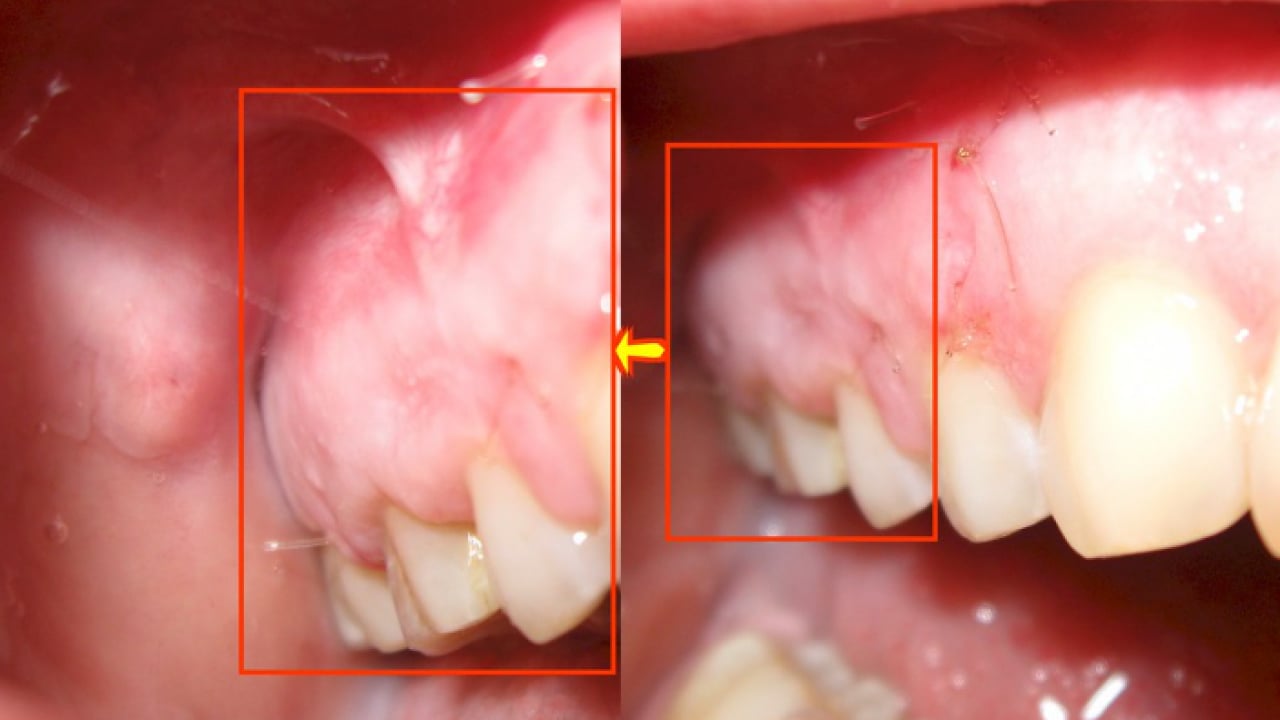

“TEDAVİ YAPILMAZSA DOKU HASARINA YOL AÇABİLİR” Kanal tedavisi yapılmazsa dişte veya vücutta hangi sorunlar görülebileceğine değinen Dr. Öğr. Üyesi Sezer, "Kanal tedavisi yapılmadığında kök ucunda oluşan lezyonlar büyüyerek kistleşebilir, büyük kemik kayıplarına ve doku hasarına yol açabilir. Dişte sürekli hassasiyet ve spontan ağrılar oluşabilir. Kronikleşmiş enfeksiyonlar bazen akut şekilde ani yüz şişliklerine dönüşebilir yahut ağrı vermese bile zaman içinde ilerleyebilir. Ağız içindeki bu enfeksiyon odakları diyabet, kalp hastalıkları gibi sistemik durumları kötü etkileyebilir. Dişlerin tedavi edilmeyip durumları kötüleştiğinde çekilmek zorunda kalınması, çiğneme fonksiyonunda bozulmaları ve bununla beraber bağışıklık sisteminin zayıflamasını da beraberinde getirir" dedi.

“TEDAVİİYİ ERTELMENİN RİSKLERİ” Tedaviyi ertelemenin diş sağlığına etkilerinden bahseden Dr. Öğr. Üyesi Sezer, "Tedavinin ertelenmesi enfeksiyonun ilerlemesine, daha büyük lezyonların oluşmasına, ağrıların artmasına ve dişin çekilme riskine yol açar. Ayrıca enfeksiyonun sistemik hastalıklarla etkileşme ihtimali artar. Erken müdahale hem dişi korur hem de komplikasyon riskini azaltır" açıklamasında bulundu.